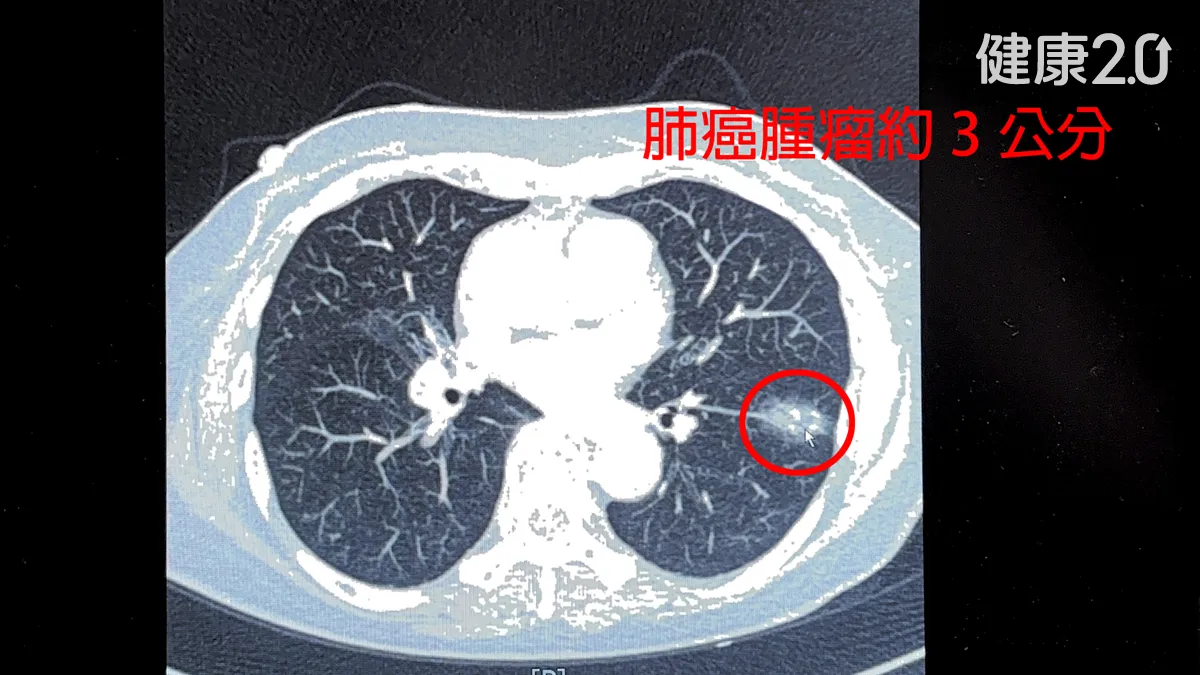

一名75歲女士今年做健檢時發現左下肺葉有3公分大的惡性腫瘤,手術摘除時,醫師發現她的肺部淋巴堅硬,血管還沾黏,會有這種狀況原來是因為患者曾得過肺結核。醫師提醒,得過肺結核的人罹患肺癌機率最高是一般人的200倍。

院方為這名案例安排透過達文西微創手術切除有肺癌腫瘤的肺葉,並以機械手臂輔助分離血管、結紮,左下肺葉3條主要的肺動脈分離後,有2條分支血管流血,所幸出血量僅200c.c.就順利止血。